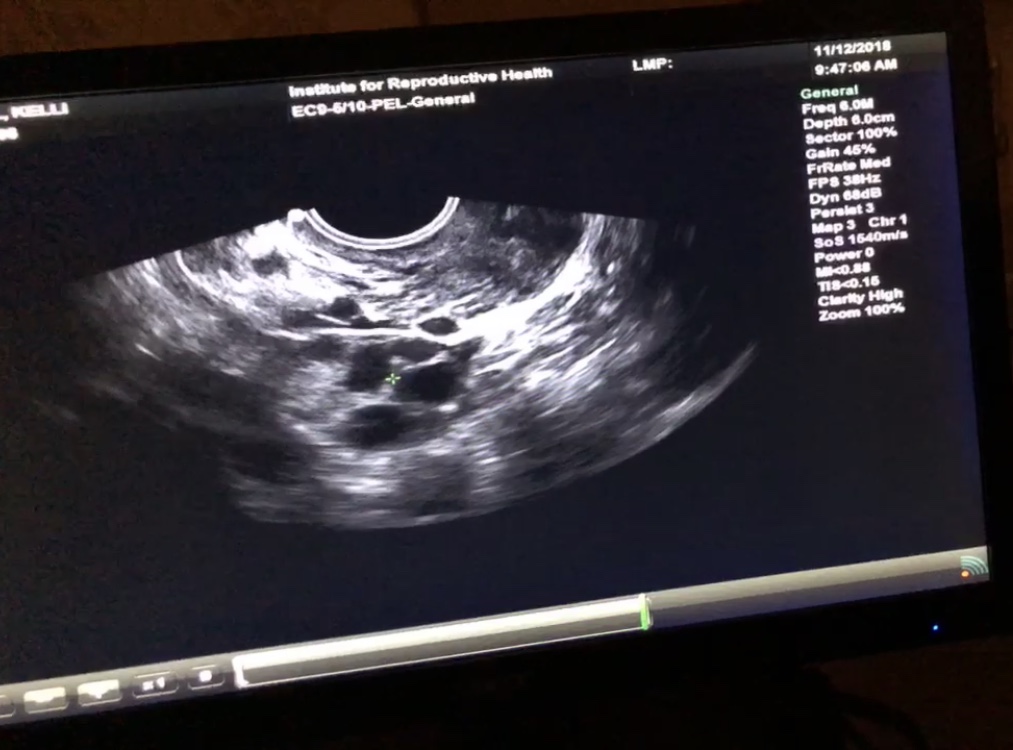

IMG_8864 Previous Next Published November 19, 2018 at 1013 × 750 in WHY I DECIDED TO FREEZE MY EGGS & MY JOURNEY TO FREEZE THEM